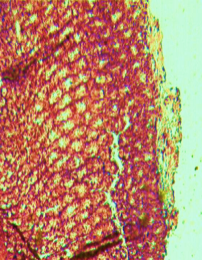

Histological evaluation of gastric lesion

Histological observation showed extensive damage of the gastric mucosa in the ulcer negative control group with necrotic lesions penetrating deeply into the mucosa accompanied by extensive edema and leucocyte infiltration of the submucosal layer (group 2).

Rats that received treatment with aqueous and methanol extracts of the leaves of D. thollonii had comparatively better protection of the gastric mucosa as seen by the reduction of ulcer area, reduced submucosal edema and leucocytes infiltration after 14 days of treatment (fig. 4).

Fig. 4: Histological study of acetic acid-induced gastric damage in rats

In fig. 4: (a’): histological section of a normal control rat: no injuries to the gastric mucosa are seen and the gastric wall is normal. ((b’): histological section of an ulcer negative control rat: there is severe destruction of the surface epithelium and necrotic lesions penetrating deeply into mucosa and submucosa layer. (c’): histological section of rats treated with Maalox (50 mg/kg): the gastric wall appears normally, but there is edema of mucosa and sub mucosa layer.(d’): the histological section of rats treated with Ranitidine (50 mg/kg): the gastric wall appears normally with all layers. (e’): the histological section of rats treated with 125 mg/kg of aqueous extract: there is mild disruption of the sub mucosal layer. (f’): histological section of rats treated with 250 mg/kg aqueous extract: there is moderate disruption of the surface epithelium. (g’): histological section of rats treated with 500 mg/kg of aqueous extract: there is mild disruption of the sub mucosal layer and edema of the muscle. (h’): histological section of rats treated with 125 mg/kg of methanol extracts: there is mild disruption of the epithelium surface and the sub mucosal layer and edema of the serosal layer. (i’): histological section of rats treated with 250 mg/kg of methanol extract: there is mild disruption of the epithelium surface and edema of the submucosal and serosal layers. (j’): histological section of rats treated with 500 mg/kg of methanol extract: there is moderate disruption of the epithelial surface although the gastric wall appears normally.